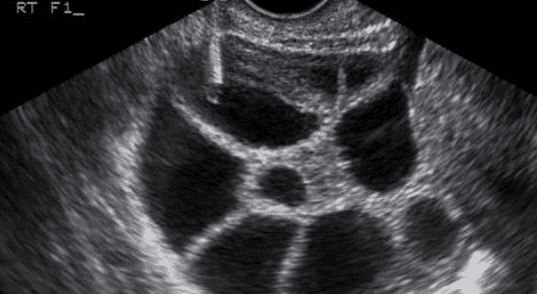

The ovum pickup procedure in IVF is performed under ultrasound guidance and mild anesthesia, ensuring that it is both safe and comfortable for the patient. A thin needle is passed through the vaginal wall to gently aspirate the mature eggs from the ovarian follicles. The entire egg retrieval process usually takes 15–30 minutes and does not require a long hospital stay.

Ultrasound-guided retrieval of eggs in the Ovum Pickup Room.